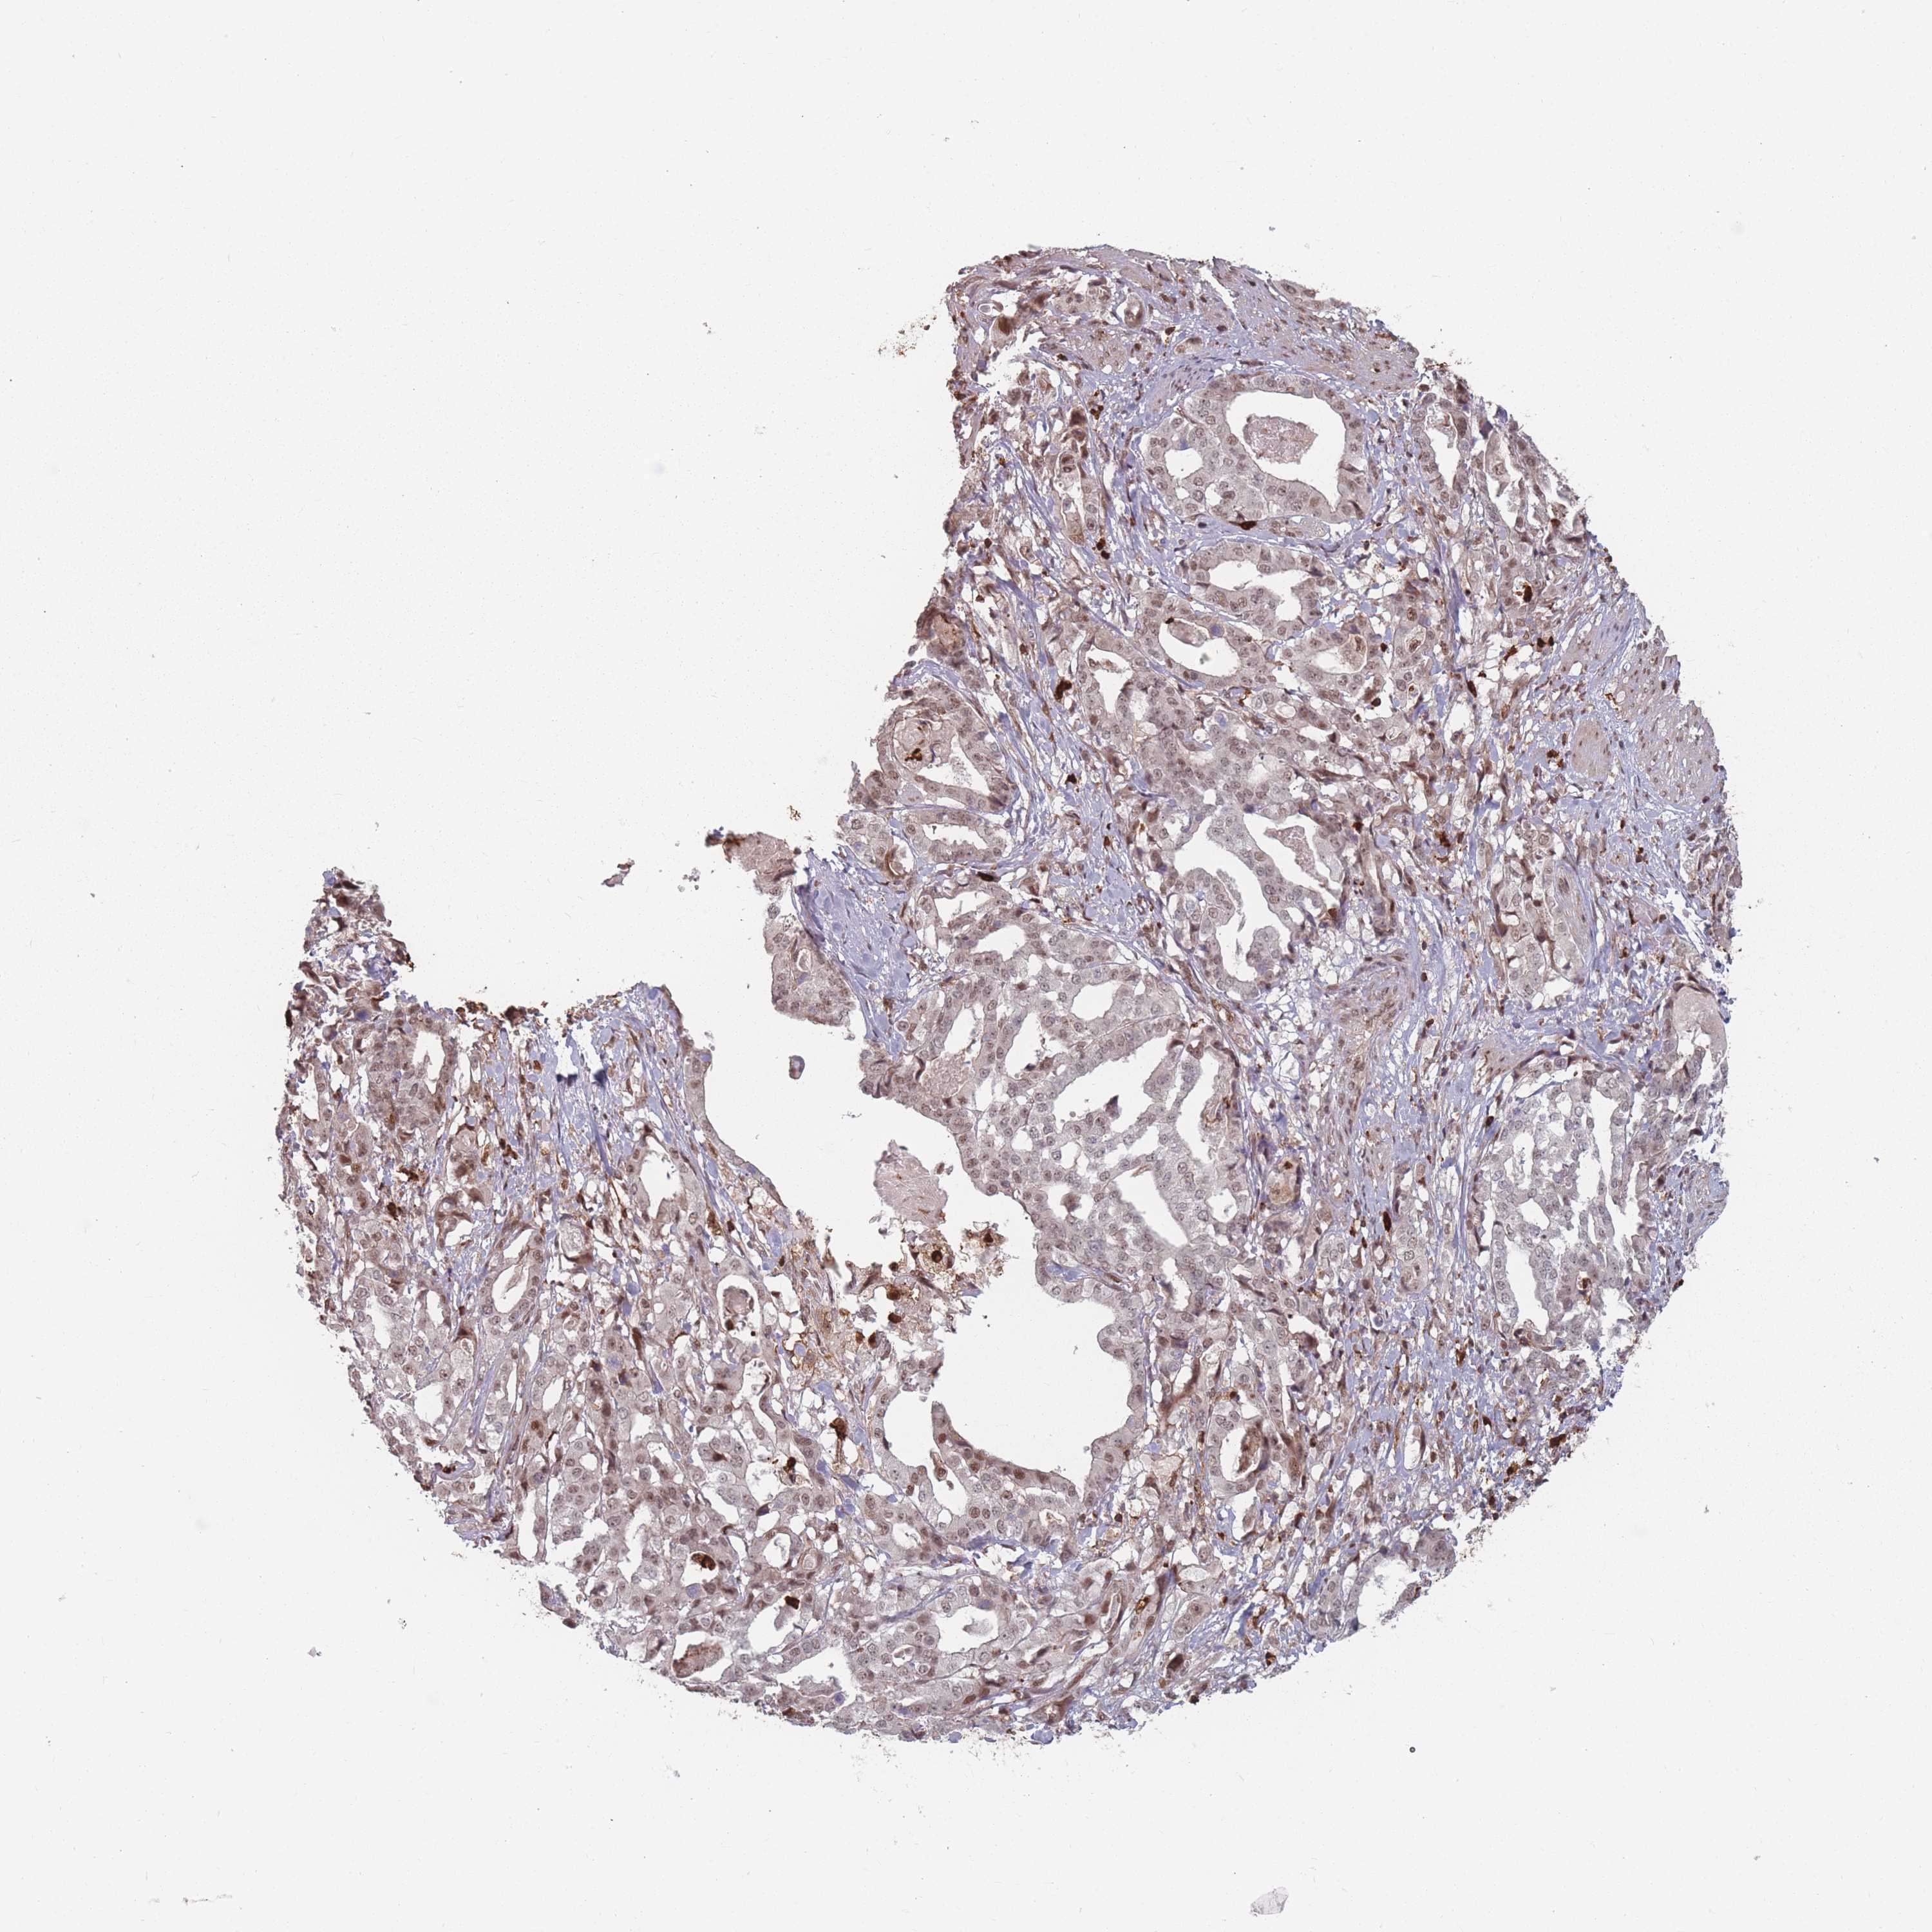

STOMACH CANCER - Protein expressioni

A mouse-over function shows sample information and annotation data. Click on an image to view it in a full screen mode. Samples can be filtered based on level of antibody staining by selecting one or several of the following categories: high, medium, low and not detected. The assay and annotation is described here.

Note that samples used for immunohistochemistry by the Human Protein Atlas do not correspond to samples in the TCGA dataset.

Antibody stainingi

Antibody staining in the annotated cell types in the current human tissue is reported as not detected, low, medium, or high, based on conventional immunohistochemistry profiling in selected tissues. This score is based on the combination of the staining intensity and fraction of stained cells.

Each image is clickable and will lead to virtual microscopy that enables deeper exploration of all samples and also displays staining intensity scores, fraction scores and subcellular localization as well as patient and tissue information for each sample.

Antibody HPA043470

Antibody HPA048143

Staining

High

Medium

Low

Not detected

Intensity

Strong

Moderate

Weak

Negative

Quantity

>75%

75%-25%

<25%

None

Location

Nuclear

Cytoplasmic/membranous

Cytoplasmic/membranous,nuclear

Adenocarcinoma, NOS